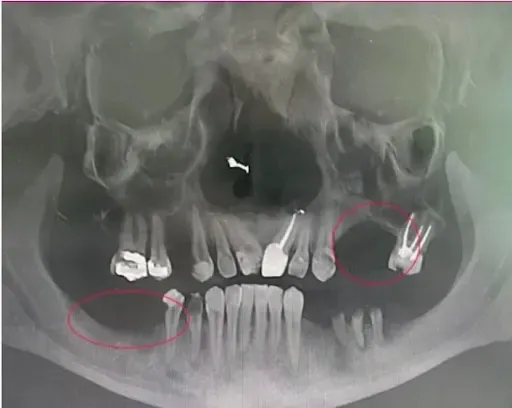

The scan below makes it easy to see how missing just one or two teeth in one part of the mouth causes significant bone loss. Look at the upper right side in the picture below. Can you see the larger curve upward? That is how much bone had disappeared because there was no tooth OR dental implant there to keep the bone stimulated.

Likewise, on the bottom left side, you can see a large downward curve because the back molars had been missing for quite some time. The longer these issues go uncorrected the more dangerous and expensive the corrections become.